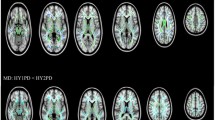

Pronounced patterns of FA differences emerged when stratifying PD participants according to HY stage. HY1 participants (n = 275) had higher FA across the entire WM skeleton (d = 0.30) as well as 4 out of 21 regions of interest (ROI) compared to controls (n = 885), with effect sizes ranging from d = 0.18 to 0.19 (all p < 0.05, false discovery rate corrected24). Implicated regions included the anterior corona radiata, anterior and retrolenticular parts of the internal capsule, and the genu of the corpus callosum. Higher FA in HY1 participants was in the 1.0–1.4% range across significant ROIs. HY2 PD participants (n = 742) had lower FA at the fornix (d = −0.26) relative to controls, a reduction in FA of 5.4%. HY3 PD participants (n = 220) had lower FA across the entire WM skeleton (d = −0.24), as well as 9 out of 21 ROIs, with the largest effect at the fornix (d = −0.33). Implicated regions include the anterior and posterior corona radiata, posterior thalamic radiation, genu of the corpus callosum, external capsule, fornix/stria terminalis, superior longitudinal fasciculus and the sagittal stratum. Lower FA in HY3 participants was in the 1.3–7.3% range across significant ROIs. HY4/5 PD participants (n = 75) had lower FA across the entire WM skeleton (d = −0.74), as well as 20 out of 21 ROIs relative to controls, with the largest effect in the fornix (d = −1.01) and remaining values increasing in magnitude from d = −0.26, representing between 1.4% and 18.9% lower FA. The only ROI not implicated in HY4/5 participants was the cingulum (hippocampal portion) (Fig. 1A; Supplementary Results 1.4.1).

HY1 PD participants displayed higher FA across the entire WM skeleton (d = 0.27) as well as 3 out of 21 ROIs, relative to matched controls (n = 275), with effect sizes ranging from d = 0.23 to 0.24. Implicated regions included the anterior corona radiata and the anterior and posterior limb of the internal capsule, representing between 0.9% and 1.5% higher FA. HY2 PD participants demonstrated significantly lower FA in the fornix (d = −0.27), relative to matched controls (n = 742), a reduction in FA of 5.6%. HY3 PD participants displayed lower FA in the fornix (d = −0.31) and the sagittal stratum (d = −0.29), relative to matched controls (n = 220), a reduction in FA of 2.1% and 6.7%, respectively. HY4/5 PD participants displayed widespread significant differences in FA across the entire WM skeleton (d = −0.56) as well as 18 out of 21 ROIs, relative to matched controls (n = 75), with effect sizes ranging from d = −0.38 to −1.09. Lower FA in HY4/5 participants was in the 3.0% to 19.0% range across significant ROIs. ROIs not implicated include the retrolenticular and posterior limb of the internal capsule and the corticospinal tract (Fig. 1B; Supplementary Results 1.4.2).

HY1 PD participants displayed lower MD across the entire WM skeleton (d = −0.19) as well as 5 out of 21 ROIs, relative to controls, with effect sizes ranging from d = −0.18 to d = −0.27. Implicated regions include the anterior and retrolenticular limbs of the internal capsule, the fornix/stria terminalis, cingulum (hippocampal portion) and the sagittal stratum. Lower MD in HY1 participants was in the 1.3–2.1% range across significant ROIs. HY2 PD participants displayed lower MD at the fornix/stria terminalis (d = −0.22), as well as 2 out of 21 ROIs relative to controls, with effect sizes of −0.19 and −0.18 at the retrolenticular limb of the internal capsule and the cingulum (hippocampal portion), respectively. Lower MD in HY2 participants was in the 1.2% to 1.9% range across the significant ROIs. HY2 participants also displayed higher MD at the fornix (d = 0.15), an increase in MD of 3.2%. There were no significant MD differences in HY3 PD participants relative to controls. HY4/5 PD participants displayed higher MD in the fornix (d = 0.69) as well as 6 out of 21 ROIs, relative to controls, with effect sizes ranging from d = 0.33 to 0.46. Implicated regions include the anterior and superior corona radiata, external capsule, genu and body of the corpus callosum and the superior fronto-occipital fasciculus. Higher MD in HY4/5 participants was in the 1.9% to 13.1% range across the significant ROIs. HY4/5 PD participants also displayed lower MD in the cingulum (hippocampal portion) (d = −0.32) relative to controls, a reduction in MD of 3.2% (Fig. 2A; Supplementary Results 1.4.3).

There were no significant differences in MD in HY1 PD participants relative to matched controls. HY2 PD participants demonstrated significantly lower MD at the fornix/stria terminalis (d = −0.22), as well as 3 out of 21 ROIs, relative to matched controls (n = 742), with effect sizes ranging from d = −0.14 to −0.19. Implicated regions include the posterior limb and the retrolenticular parts of the internal capsule as well as the cingulum (hippocampal portion). Lower MD in HY2 participants was in the 0.8% to 2.0% range across the significant ROIs. These participants also showed higher MD at the fornix (d = 0.15), an increase in MD of 3.3%. There were no significant MD differences in HY3 PD participants relative to matched controls, while HY4/5 PD participants displayed significantly higher MD at the fornix (d = 0.72) relative to matched controls, an increase in MD of 13.0% (Fig. 2B; Supplementary Results 1.4.4).

We found significantly higher FA in HY1 participants across the entire WM skeleton, lower FA of the fornix in HY2 participants, and lower FA across the vast majority of the WM skeleton in participants at HY stages 3 and 4/5. While the study is cross-sectional, we can see evidence of a progression of effect sizes, where results from early disease stages present as very small effects, while those at advanced disease stages showing medium and large effect sizes. In the HY1 PD participants, the largest effect sizes were found for the higher FA in the internal capsule and anterior corona radiata. These structures are key components of the cerebello-thalamo-cortical and basal ganglia-cortical loops and likely play an important role in the pathophysiology of tremor in PD. It has been suggested that tremor signals originating in the basal ganglia ascend via the ventrolateral nucleus of the thalamus through the internal capsule to the corona radiata where they radiate out to the cortex26. One study found that increased FA is associated with tremor-dominant PD, relative to postural instability-gait disturbance PD, impacting multiple brain regions including the corpus callosum, forceps minor, bilateral thalamic radiation, bilateral superior and inferior longitudinal fasciculi and the left sagittal stratum, suggesting an important relationship between this motor phenotype and DTI abnormalities in PD27. The fornix also shows among the largest effect sizes in PD; FA was significantly reduced here in HY2, HY3 and HY4/5 participants. The fornix is a major hippocampal output structure that traverses longitudinally from the mesial temporal lobes to the diencephalon and basal forebrain, and it plays a key role in cognition and episodic memory recall28. Here we show that this structure is greatly impacted in PD, with a significant correlation between FA and cognitive performance.

We identified significantly lower MD across the entire WM skeleton at the HY1 stage, while in HY2, this result was confined to the internal capsule, fornix/stria terminalis and the cingulum (hippocampal portion). In HY3, there were no significant differences in MD, while HY4/5 participants showed significantly higher MD at widespread regions of interest. Some of the significant MD findings were not observed when comparing PD cohorts to age- and sex-matched controls, with only the most robust effect sizes remaining significant. In our correlational analyses, the effect sizes generated at the matched and unmatched levels of analysis had the same direction and were highly correlated, suggesting that the lack of significant results when comparing MD in HY3 and HY4/5 groups with age- and sex-matched controls are likely due to differences in sample size and statistical power, as well as removing confounding effects. Similar to our results for the FA analyses, in HY1 and HY2 participants large effect sizes were found for regions of interest in the internal capsule, further highlighting this region as an important neuroanatomical structure in PD. In HY4/5 participants, we also found significantly higher MD in the fornix, and MD of the fornix was inversely correlated with performance on the MoCA test.